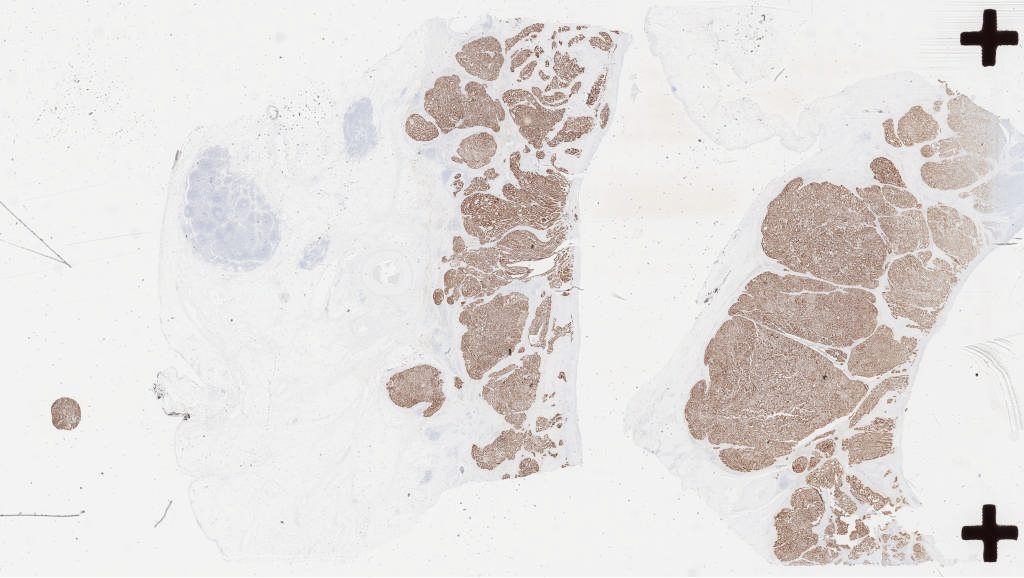

Case3 eber 1i.svs

143424

x

80827

@

40X